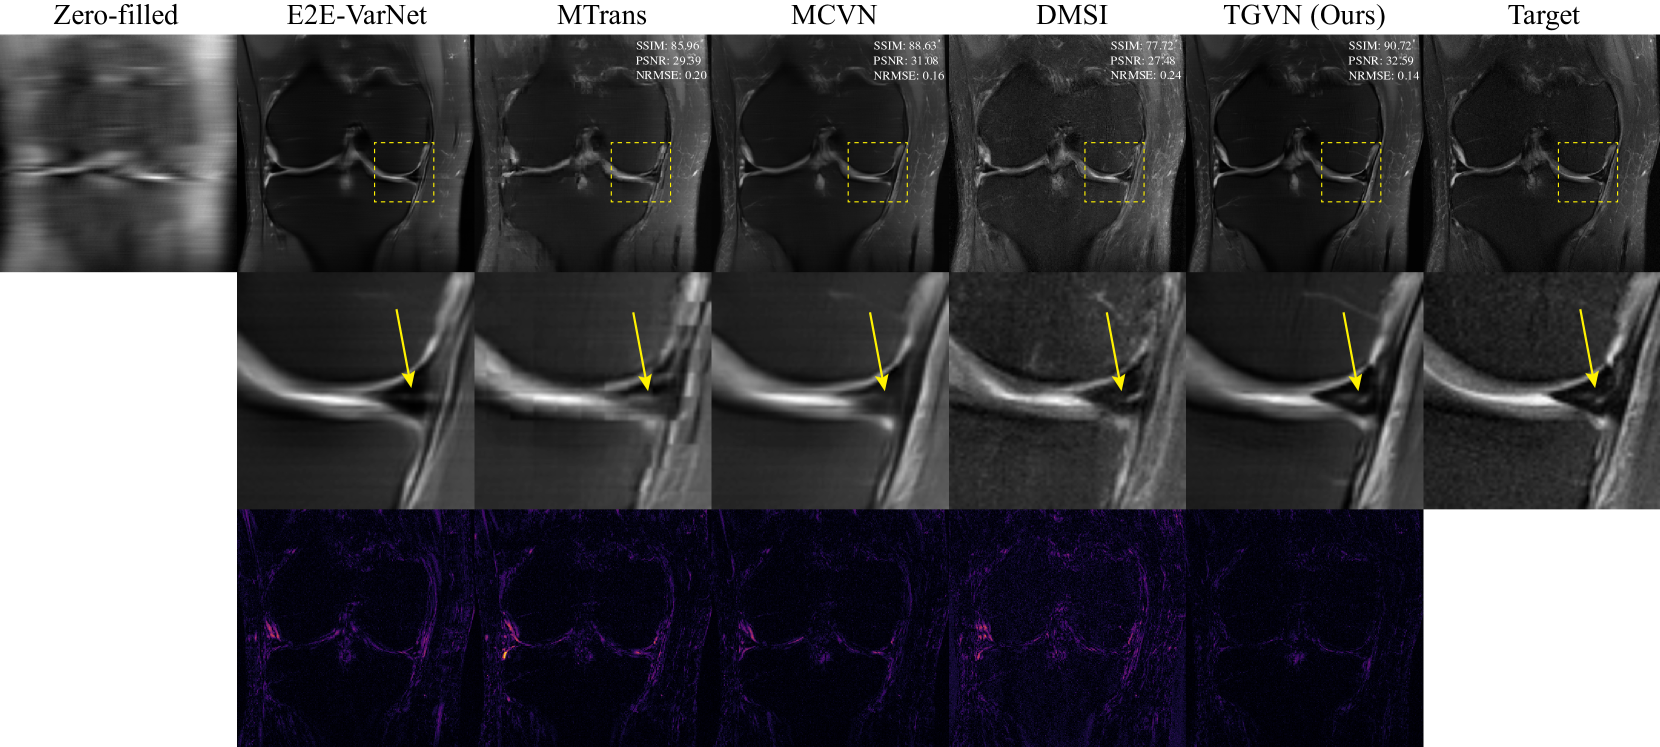

Set I – 20×20\times20 × Under-sampled Main Information and 2×2\times2 × Under-sampled Side Information

We applied an overall 20×20\times20 × undersampling mask to the PDFS measurements, with random outer undersampling and a 3%percent33\%3 % fully-sampled center. A 2×2\times2 × equispaced under-sampling mask with no fully-sampled center was applied to the PD measurements. Fig. 3(a) shows the reconstruction results for coronal PDFS images with and without using the side information. At 20×20\times20 × acceleration, side information aids the reconstruction significantly while reconstruction without side information results in the loss of various essential features. Fig. 4 compares TGVN reconstructions with reconstructions using multiple baselines that use side information. MTrans and MCVN exhibit significant blurring of anatomical features, and DMSI suffers severely from noise amplification, which is seen clearly in the absolute difference images. The output of TGVN is significantly superior: both overall sharpness and assorted anatomical details are better preserved in the TGVN reconstructions. Furthermore, the meniscus tear region is distinctly more noticeable with TGVN, highlighting that it is more effective in leveraging the side information to preserve key features in the image despite highly sparse measurements.

Refer to caption

Figure 4: Knee image reconstructions from Set I showing the effectiveness of TGVN in leveraging side information. TGVN is able to reconstruct a high-quality image even at challenging acceleration levels of 20×20\times20 ×, in comparison to various baselines. The meniscus tear, illustrated in the ground truth image and reconstructions with a yellow arrow, is notably more visible in the TGVN reconstruction than in baseline reconstructions. Top: Full field of view images. Middle: Zoomed-in regions indicated by dashed yellow boxes in the top row. Bottom: Absolute differences between each reconstruction and the ground truth, with a consistent color mapping to highlight error magnitudes. TGVN has the smallest error.

Table 1 reports the quantitative evaluation of TGVN as compared with baselines in both sets of experiments. TGVN achieves the best average score across all metrics, proving that it is more effective than any of the baselines in utilizing side information. In each experiment and for each evaluation metric (SSIM, PSNR, and NRMSE), a Wilcoxon signed-rank test rejected the null hypothesis at a significance level of 5%percent55\%5 %, indicating that there is a statistically significant difference between sourssubscript𝑠ourss_{\text{ours}}italic_s start_POSTSUBSCRIPT ours end_POSTSUBSCRIPT and sbasesubscript𝑠bases_{\text{base}}italic_s start_POSTSUBSCRIPT base end_POSTSUBSCRIPT. We provide additional details regarding reconstructions and evaluation results in the Supplementary Material, showing that TGVN has superior performance for almost all examples in the test dataset for each experiment.